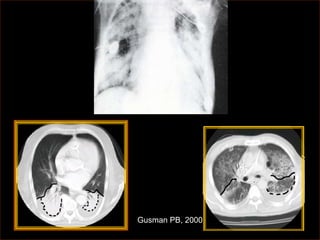

Gusman PB, 2000

Níveis de oxigênioe aumento da resistência pulmonar Hypoxemia causes Regional vasodilation in systemic hypoxia vessels Piora alta PaCO2 baixo pH Aumento do fluxo reduz o vasoconstriction of efeito hipoxêmico small pulmonary arteries